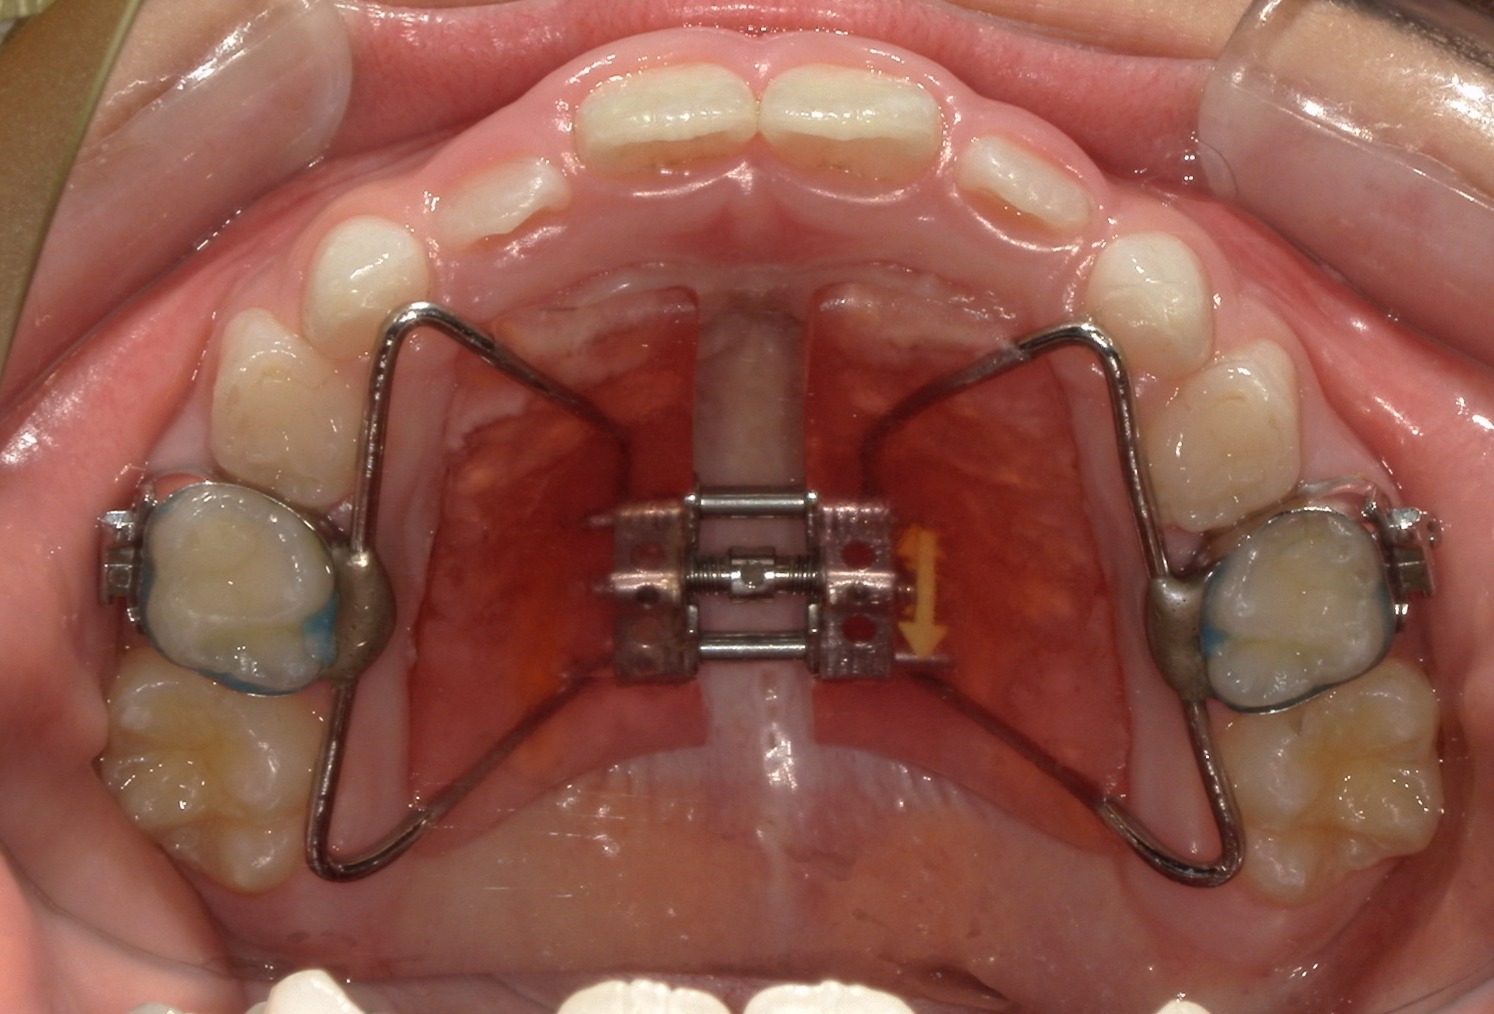

受け口(上顎歯列弓狭窄による臼歯部交叉咬合)

6歳 男性

治療法

上顎歯列拡大による交叉咬合の改善

装置

急速拡大装置

使用装置写真

費用

495,000円(税込)

期間

約1年半

付記

上顎がかなり狭窄した状態でした。固定式拡大装置で歯列および顎骨を拡大し、奥歯のかみ合わせも改善しています。

中学生以降になると骨が固くなりこのようにキレイには拡大できないため早期治療が功を奏した例です。

2期治療のための精密検査が必要です。

リスク:歯肉退縮、歯根吸収、後戻り、予期せぬ成長